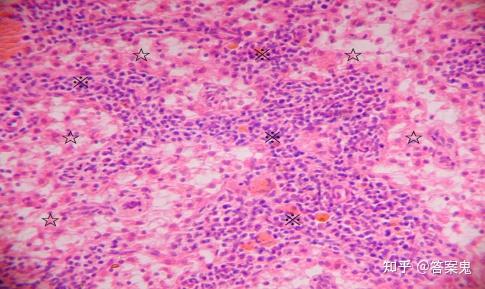

图10-7淋巴结的髓质(淋巴结 he染色10×10) 图示淋巴结髓质的髓索(※)